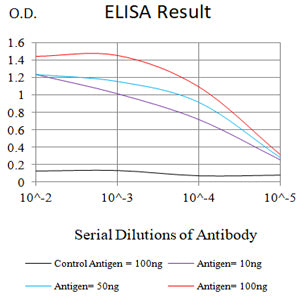

分类: 科研抗体货号: 31981别名: SGB; DGSX; MXR7; SDYS; SGBS; OCI-5; SGBS1; GTR2-2应用: WB,IHC,FCM反应种属: Human, Mouse